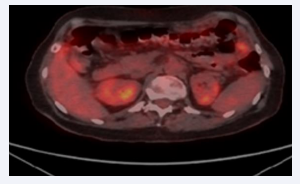

Treatment continues with carboplatin/paclitaxel and trastuzumab with stable desease as determined by imaging, against the backdrop of an upward trend in tumor markers and with relatively severe patient tolerability. After eleven courses, PET/CT reports progression of peritoneal dissemination, with the formation of “omentum cake”, the appearance of new metabolically active peritoneal deposits, as well as an increase in the volume of ascites fluid in the pelvis and perihepatic (PFS6 = 11 months) (Figure 1).

Progression of peritoneal carcinomatosis.

Figure 1: Progression of peritoneal carcinomatosis.